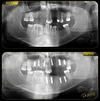

الصور